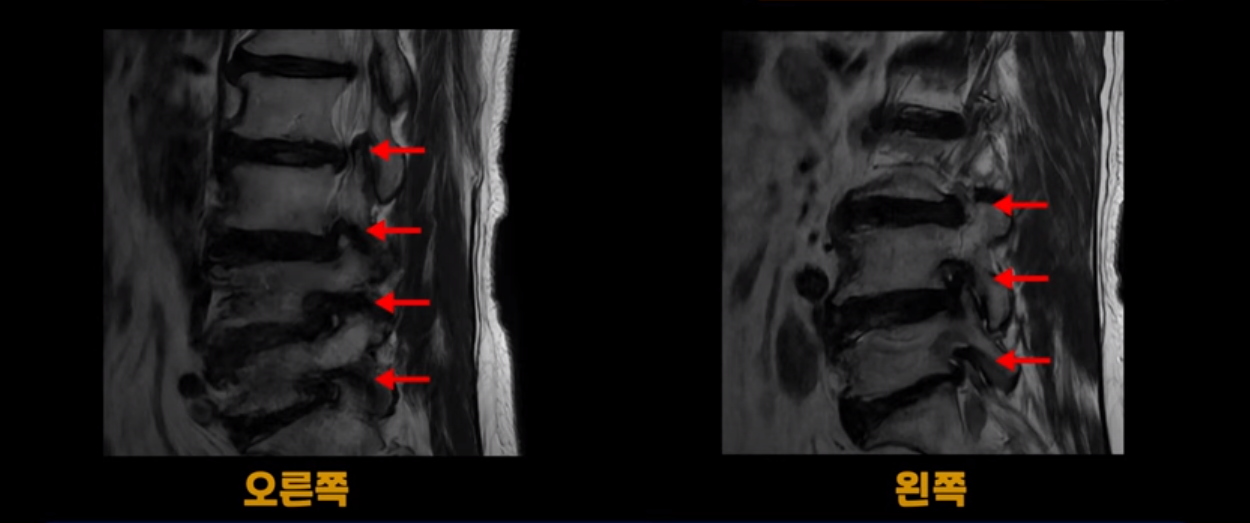

이 환자분은 MRI로 보면 허리 여러 마디가 신경이 매우 심하게 눌려 보이는 분입니다. 이분 MRI를 보면서 간단히 설명해 드린 후 어떻게 이렇게 신경이 심하게 눌린 환자분이 수술 없이 근육신경재활치료로 좋아질 수 있는지, 다리가 아파 걷지 못하는 환자가 어떻게 안 아프고 잘 걸을 수 있게 되는지, 10년 동안 괴로웠던 양 발의 시린 증상은 어떻게 사라질 수 있는지, 치료는 어떻게 하는지 자세히 설명 드리겠습니다.

MRI 보시면 (2-8) 허리의 5마디가 전부 다 심하게 퇴행되어 있습니다.

5마디 전부 다 심한 중심성 협착이 있습니다.

이렇게 모두 다 심하게 막히는 경우는 드문데요. 또한 오른쪽, 왼쪽 신경이 빠져나가는 추간공도 다 심하게 막혀있습니다.

오른쪽, 왼쪽 이렇게 신경 구멍들이 다 좁아지고 신경이 눌리니까 양쪽 다리가 발바닥까지 아파서 걷기 어렵고 양쪽 발이 10년 넘게 시린 겁니다. 당연히 수술해서 눌린 신경을 풀어줘야 한다고 들으셨는데요. 이런 환자분을 어떻게 수술 없이 치료할까요? 지금부터 설명해 드립니다.